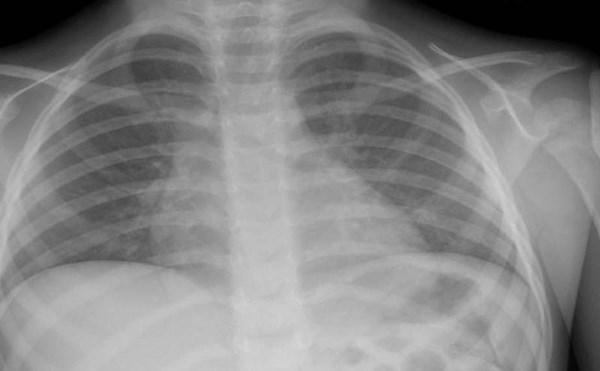

Hydrocarbon Exposure

The patient is a 2-year-old male with a history of bronchiolitis who presents to the ED with his mother after ingesting “TIKI® torch fuel.”